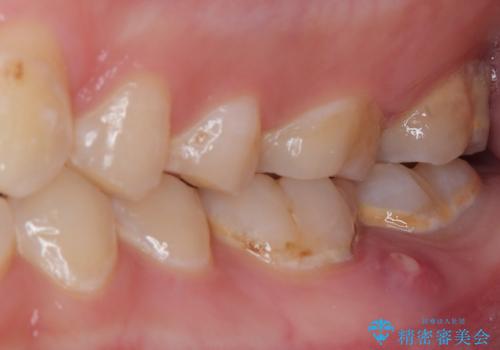

- 食事などで噛んだときに奥歯に痛みを感じるとのことで来院された患者様です。

奥に埋もれている親知らずが原因でむし歯になり、以前に根管治療を行った歯が痛みの原因であり、再度根管治療が必要な状態でした。